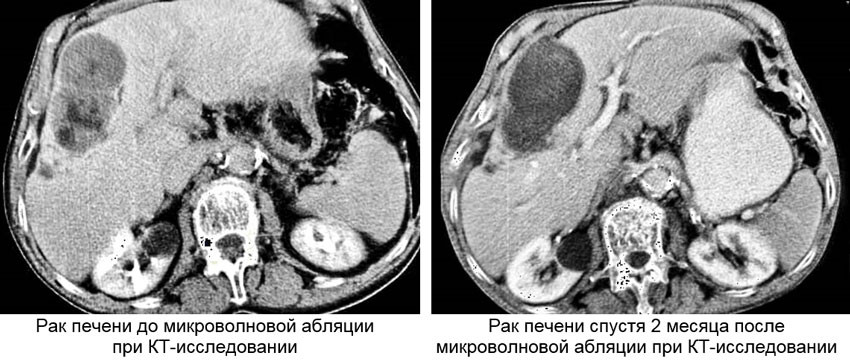

Микроволновая абляция печени

Рак печени является крайне коварным онкологическим заболеванием. Без лечения средняя продолжительность жизни пациентов с диагнозом гепатоцеллюлярный рак печени не превышает 6 месяцев, а медиана выживаемости пациентов с метастатическим колоректальным раком не превышает 5 месяцев. Единственными радикальными методами лечения первичного или метастатического рака печени является оперативное вмешательство — хирургическая резекция и трансплантация. Однако по объективным причинам большинство пациентов с первичным или метастатическим раком печени являются неоперабельными. Так, согласно статистическим данным лишь у 20% пациентов с диагнозом гепатоцеллюлярный рак возможно выполнить резекцию или трансплантацию. При метастатическом колоректальном раке резекция возможна не более чем в 10 — 20% случаев, при этом послеоперационная летальность может достигать 5%. Неоперабельность пациентов с раком печени связана как с прогрессивной стадией заболевания и неудобном для резекции расположением опухоли, так и с общим неудовлетворительным состоянием пациента из-за наличия различных сопутствующих заболеваний, в том числе ограниченными функциональными резервами печени, что в совокупности влечет за собой высокие потенциальные риски оперативной хирургии. Если в качестве метода терапии первичного или метастатического рака печени рассматривать системную химиотерапию, в том числе с использованием таргетных препаратов, то ее отдаленные результаты крайне неутешительны. К примеру, применение современных схем химиотерапии у пациентов с метастатическим раком печени позволяют достичь медиану выживаемости в 2 года, однако показатель 5-летней выживаемости составляет 0%.

В связи с этим, в особенности в последние годы, активно внедряются в повседневную клиническую практику различные методы локальной терапии для лечения неоперабельного рака печени, к которым относятся радиочастотная абляция, микроволновая абляция, лазерная абляция, ультразвуковая абляция (HIFU или ФУЗ-абляция), необратимая электропорация (Нано-Нож) и криоабляция. Однако только 3 технологии из перечисленных в 2016 году были включены в клинические рекомендации Европейского Сообщества Медицинской Онкологии (EMSO) по лечению метастатического колоректального рака — радиочастотная абляция, микроволновая абляция и криоабляция.

Накопленный мировой опыт доказывает, что микроволновая абляция первичного и метастатического рака печени является высокоэффективным методом лечения и в ряде случаев по эффективности даже не уступает хирургической резекции.